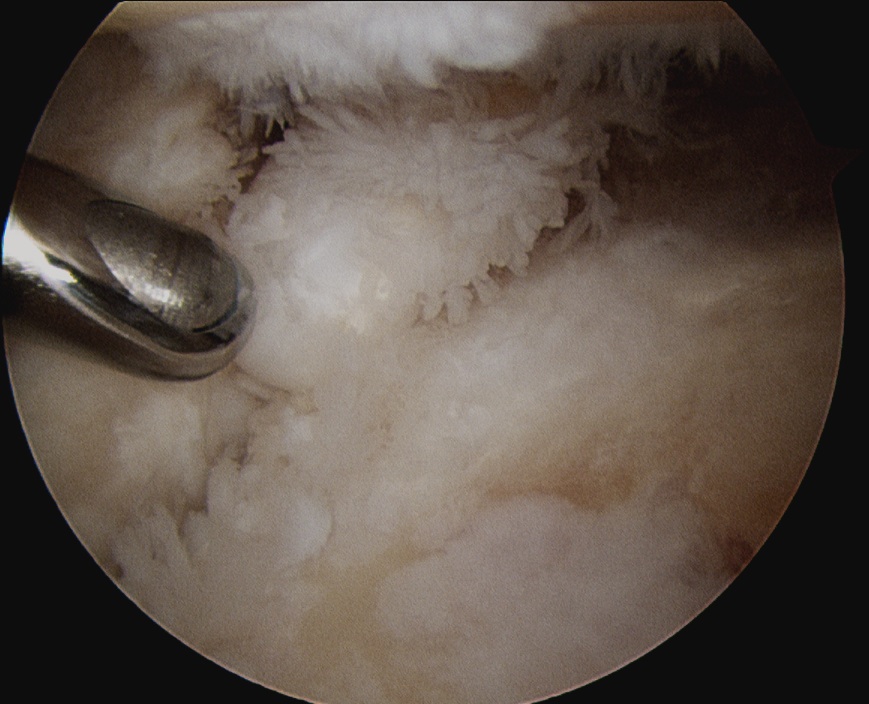

Arthroscopic Synovectomy

Kanbe et al. Eur J Orthop Surg Traumatol 2015

- arthroscopic synovectomy and capsular release for 54 RA shoulders

- mean follow up 5 years

- 67% receiving biologic treatments

- improvements in function and ROM